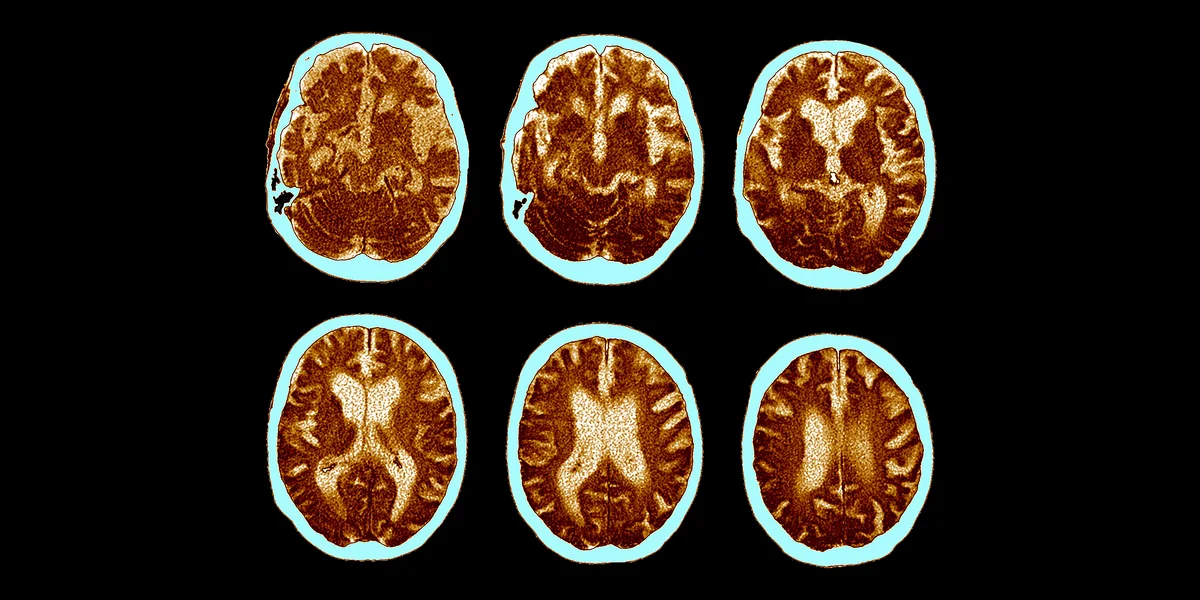

Hohlräume und die weißen Regionen weiten sich bei Menschen mit Alzheimer aus: das Gehirn schrumpft Foto: Science Photo Library/ZEPHYR/getty images

„Es geht lange, dass man nur selbst merkt, dass etwas nicht stimmt“, sagt Hilde, 82, bei einem Treffen in einem Berliner Café. Die pensionierte Ärztin ist groß, fit, schlank. Die rote Lesebrille hebt sich markant von den kurz geschnittenen, dichten, weißen Haaren ab. 2008 bemerkte sie das erste Mal, dass ihr Gedächtnis sie im Stich ließ. Sie ließ ein MRT machen – keine Auffälligkeiten. Acht Jahre später ließen sich die Symptome nicht mehr ignorieren: zunehmende Vergesslichkeit, Orientierungsschwierigkeiten. „Ich ahnte, was los ist.“ Erneut MRT und eine Lumbalpunktion – eine Untersuchung des Hirnwassers –, die gängigen Verfahren, um eine Demenz- oder Alzheimererkrankung zu klären. „Es war ein Schock. Das MRT zeigte: Das Großhirn war deutlich geschrumpft.“

Sie ist eine neurodegenerative Erkrankung, die nur in den wenigsten Fällen auf Vererbung zurückzuführen ist. Die genauen Ursachen und biochemischen Prozesse im Gehirn sind nicht geklärt. Kennzeichnend ist die kontinuierliche Zerstörung von Nervenzellen und Zellverbindungen durch veränderte Eiweiße, die sich – durch sogenannte Fibrillen mit Tau-Protein und Plaques aus Beta-Amyloiden – innerhalb und außerhalb von Nervenzellen ablagern. Sie führen dazu, dass die Nervenzellen nicht mehr untereinander kommunizieren können und am Ende absterben.

Wenn jüngere Menschen an Alzheimer erkranken, liegt meist die seltene monogenetische Variante vor. Heute weiß man, dass es sich so bei der ersten Alzheimer-Patientin verhielt. 1901 bemerkte der Psychiater und Neuropathologe Alois Alzheimer bei der erst 51-jährigen Auguste Deter geistige Verwirrung, Orientierungslosigkeit und Aggressivität. Nach ihrem Tod 1906 ließ er Gewebeproben ihres Gehirns untersuchen und stellte eine geschrumpfte Hirnrinde und Eiweißablagerungen fest. Lange hat man diese Krankheit, die seither den Namen ihres Entdeckers trägt, nicht weiter erforscht und ihren Fall nicht mit Altersdemenz in Verbindung gebracht. Heute weiß man, dass beide Formen der Demenz die gleichen neuropathologischen Charakteristika aufweisen.